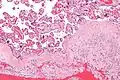

Chronic deciduitis is a type of long-lasting inflammation that arises in pregnancy and affects the endometrial stromal tissue (decidua).

It is associated with preterm labour.[1] The diagnosis rests primarily on the presence of plasma cells.[2]

Intermed. mag.

Intermed. mag. High mag.